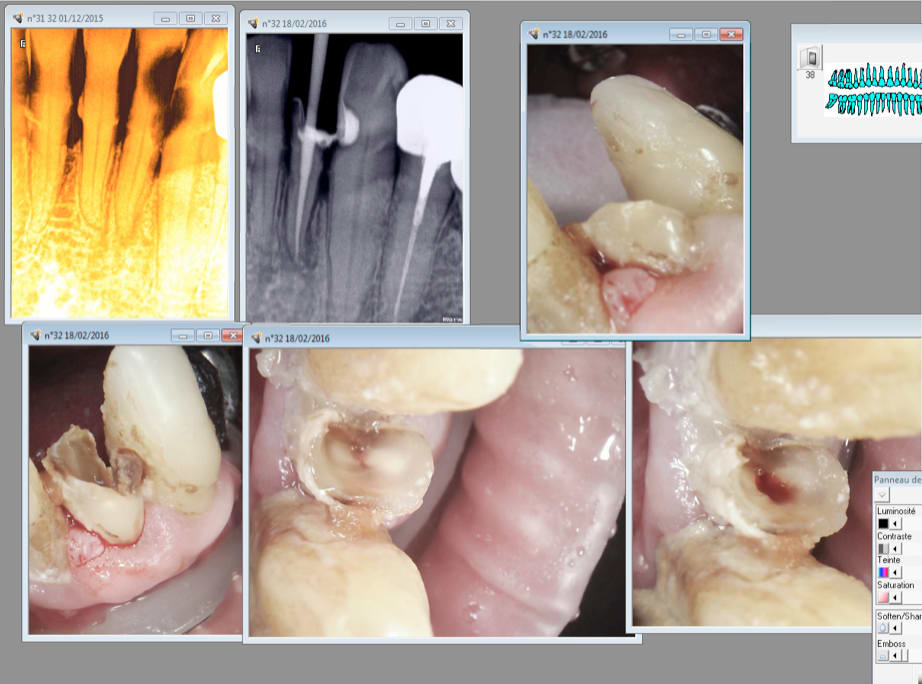

il s'agit d'un patient de 58 ans de bon état général, il présente des abrasions dentaires sévères au niveau du secteur incisivo-canin inférieur avec absence des dents postérieures.

le patient decide de mette des implants sur les secteurs postérieurs et un bridge englobant toutes les dents inférieures (implants et dents résiduelles). Et donc j'ai procéder aux traitements canalaires de ses incisives (test de sensibilité positif) pour ensuite passer à la taille; et là aucune lime (meme la plus fine) n'a pu franchir l'entrée canalaire; sachant qu'il apparaissait un filet de lumière canalaire sur la RVG. aucun resultat alors j'ai essayé avec la rotation continue mais j'ai creer un faux canal. alors après un temps fou passé sur ce patient j'ai mi une mèche d'hypochlorite à l'entrée du canal et un pansement.

3 Tu fais l'endo en suivant la différence de couleur de la dentine tertiaire qu'a élaboré la pulpe en se rétractant.

Faut pas s'emmerder avec des cavités d'accès à la con sur des incisives et canines c'est le meilleur moyen de faire des conneries. Tu rases tu vois bien le centre de la dent avec la couleur de la dentine réactionnelle tu descends dans l'axe un coup de sx et terminé.

Là tu les rases tes 2 ratiches et après c'est à l'aise. Tu es peut etre bon dans l'axe mésio distal ( enfin façon de parler lol !) mais tu te gaufres lamentablement dans l'axe vestibulo -lingual.